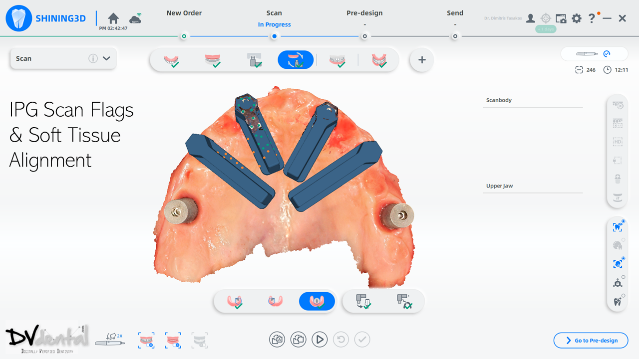

In this case, we encountered a problem: while the MUA of the four anterior implants were compatible with the IPG scan bodies, the two posterior implants were not compatible with the IPG scan bodies. Therefore, we will scan the two posterior implants using normal 3D reconstruction technology (in the soft tissue scan, placing two standard scan bodies on the MUA of the two posterior implants) and then scan the anterior implants with IPG technology (placing the IPG scan bodies on the MUA of the four anterior implants).

In the next stage, alignment between the IPG scan bodies and the soft tissue, along with the standard scan bodies, will be performed to obtain a digital model with six scan bodies of the Implants.

Fig 11,12: Step 6, install and scan the coded scanbody using photogrammetry technology